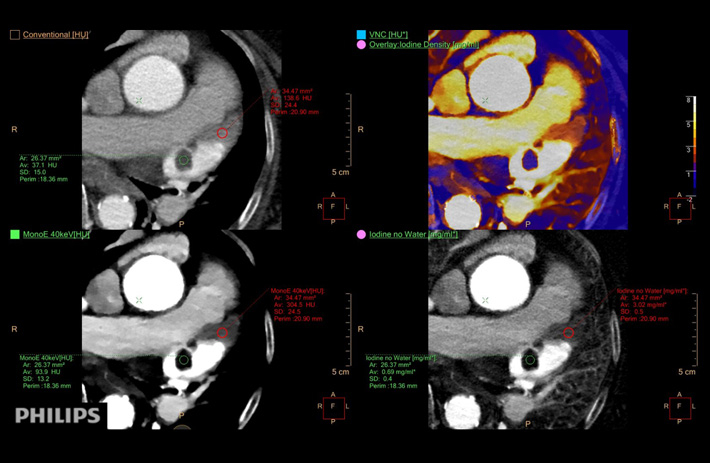

Mit dem Spektral-Detektor-CT werden Spektraldaten automatisch bei jedem Scan erfasst. Die Informationen stehen jederzeit auf der Scankonsole, der CT-Workstation sowie an jedem PACS-Arbeitsplatz zur Verfügung, sodass es nicht notwendig ist, den Patienten erneut zu scannen, bspw. wenn initial zufällige Anomalien festgestellt wurden. Dadurch profitieren Anwender durch eine höhere Diagnosesicherheit und weniger Nachuntersuchungen auf anderen bildgebenden Systemen. Unsere Fallsammlung zeigt, welchen klinischen Mehrwert der Spektral-Detektor-CT in unterschiedlichsten Anwendungsbereichen in der klinischen Routine bringt. Jede Woche gehen neue Fälle live.